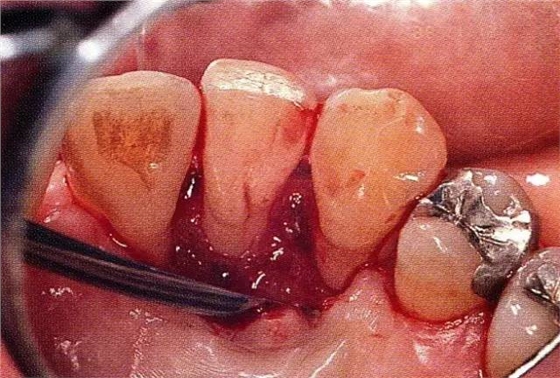

▲圖7-4術(shù)后1年2個(gè)月再翻開看的情況。與圖7-1的骨缺損狀態(tài)相比可知形成了臨床性骨再生。

▲圖7-5此狀態(tài)下,左下5的遠(yuǎn)中存在牙槽骨不平整,因此進(jìn)行了骨修整。同時(shí),將骨膜留存,進(jìn)行了齦瓣根尖側(cè)移動(dòng)術(shù),去除了牙周袋。